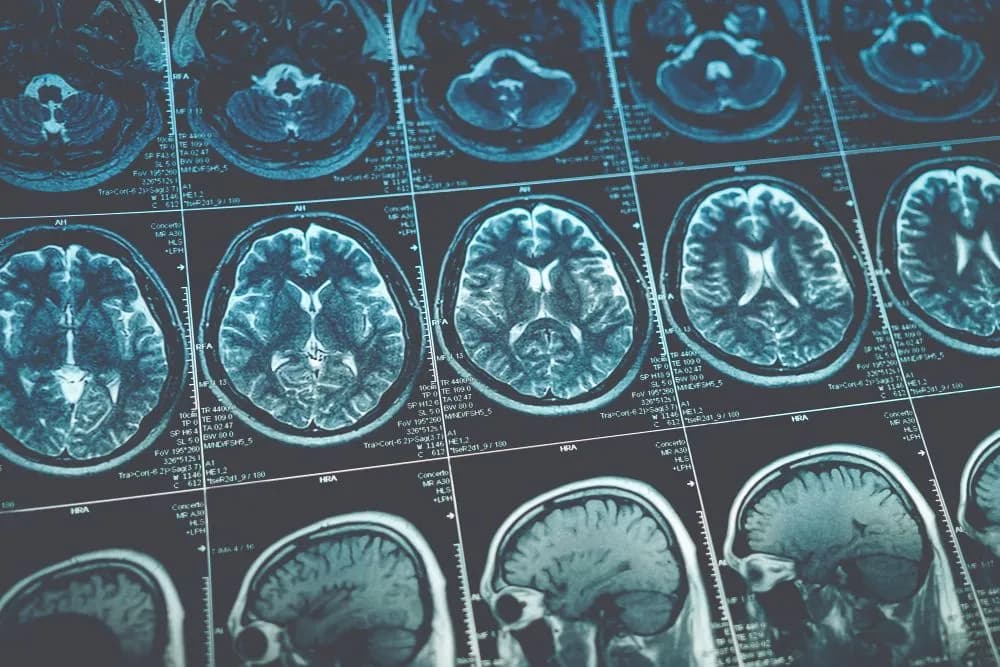

Poznaj objawy guza w głowie, takie jak bóle głowy i zmiany w widzeniu. Dowiedz się, kiedy szukać pomocy medycznej dla skutecznego leczenia.